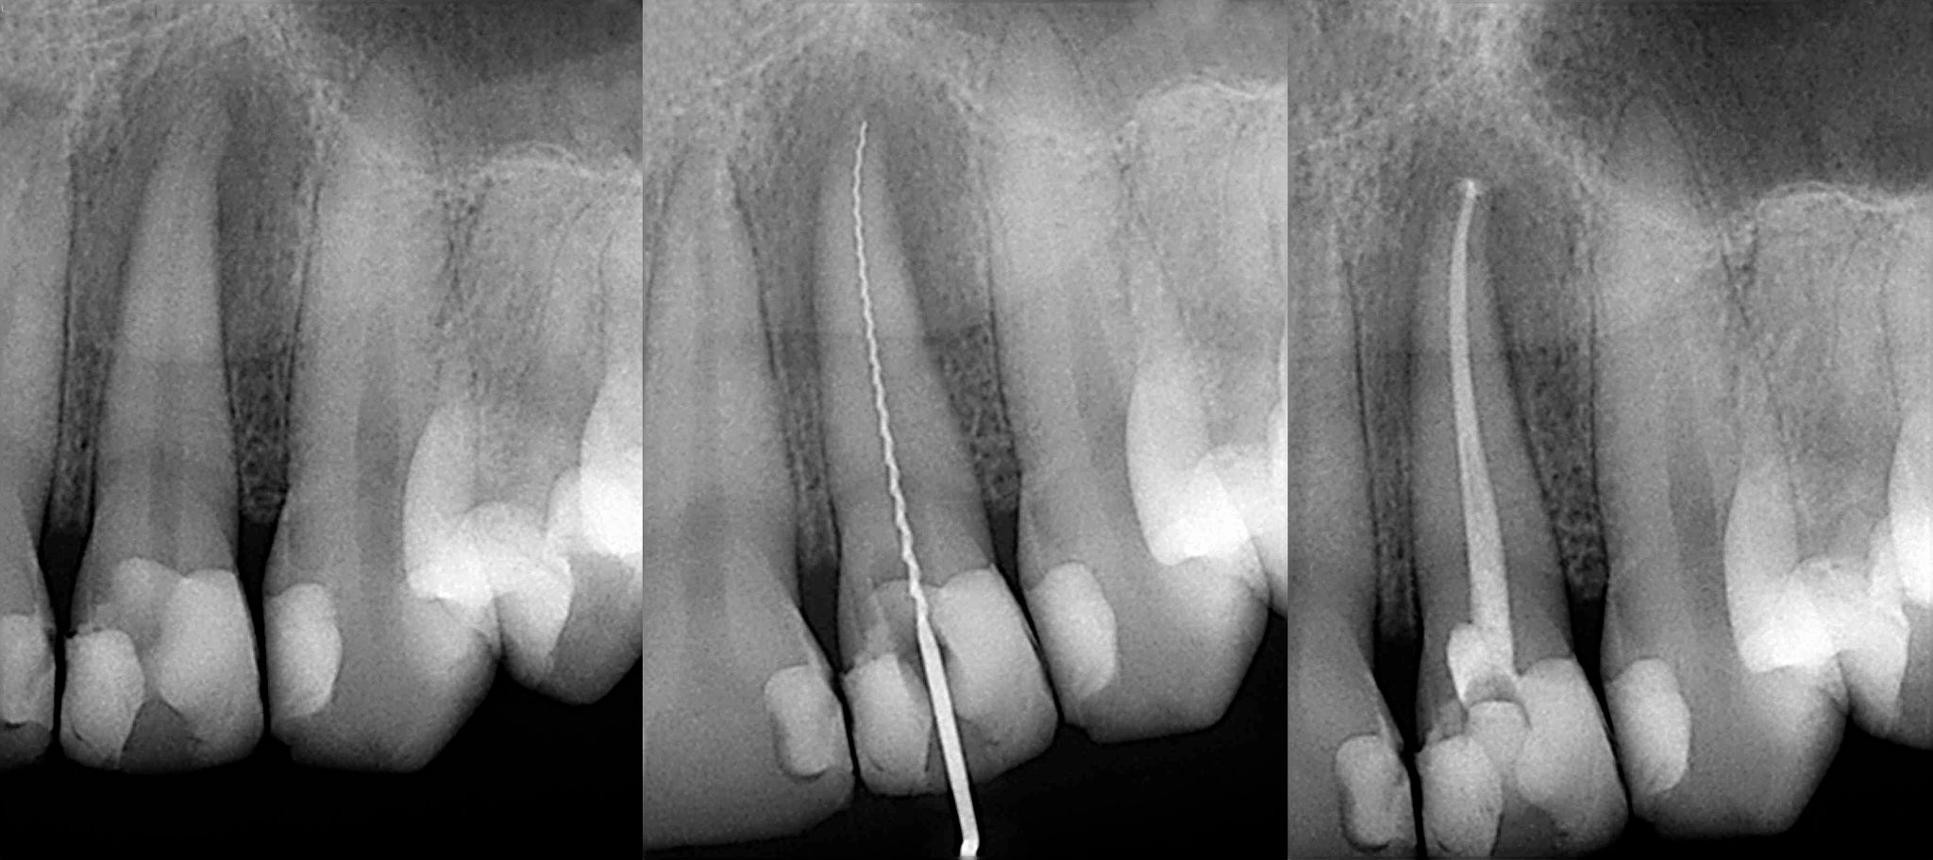

4. Dental X-Rays (Most Important Step)

X-rays play a crucial role in diagnosing the need for RCT

treatment. They help dentists see:

- Infection at the root tip

- Bone loss around the tooth

- Deep cavities reaching the pulp

If the infection is visible on an X-ray, root canal treatment in

Bangalore is usually necessary.

Modern dentistry has made RCT treatment virtually painless:

- Performed under local anesthesia

- Advanced tools ensure precision

- Minimal discomfort during and after the procedure

In fact, the procedure relieves pain rather than causing it.